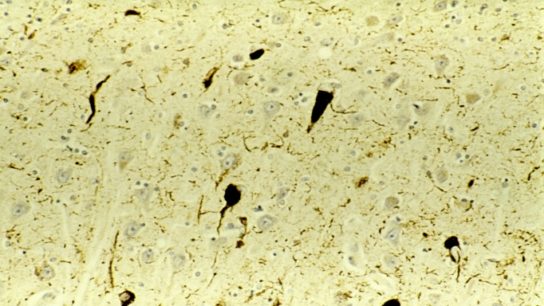

Diagnosis of rapidly progressive dementias is difficult due to broad pathology and underdeveloped diagnostic criteria for clinical settings.